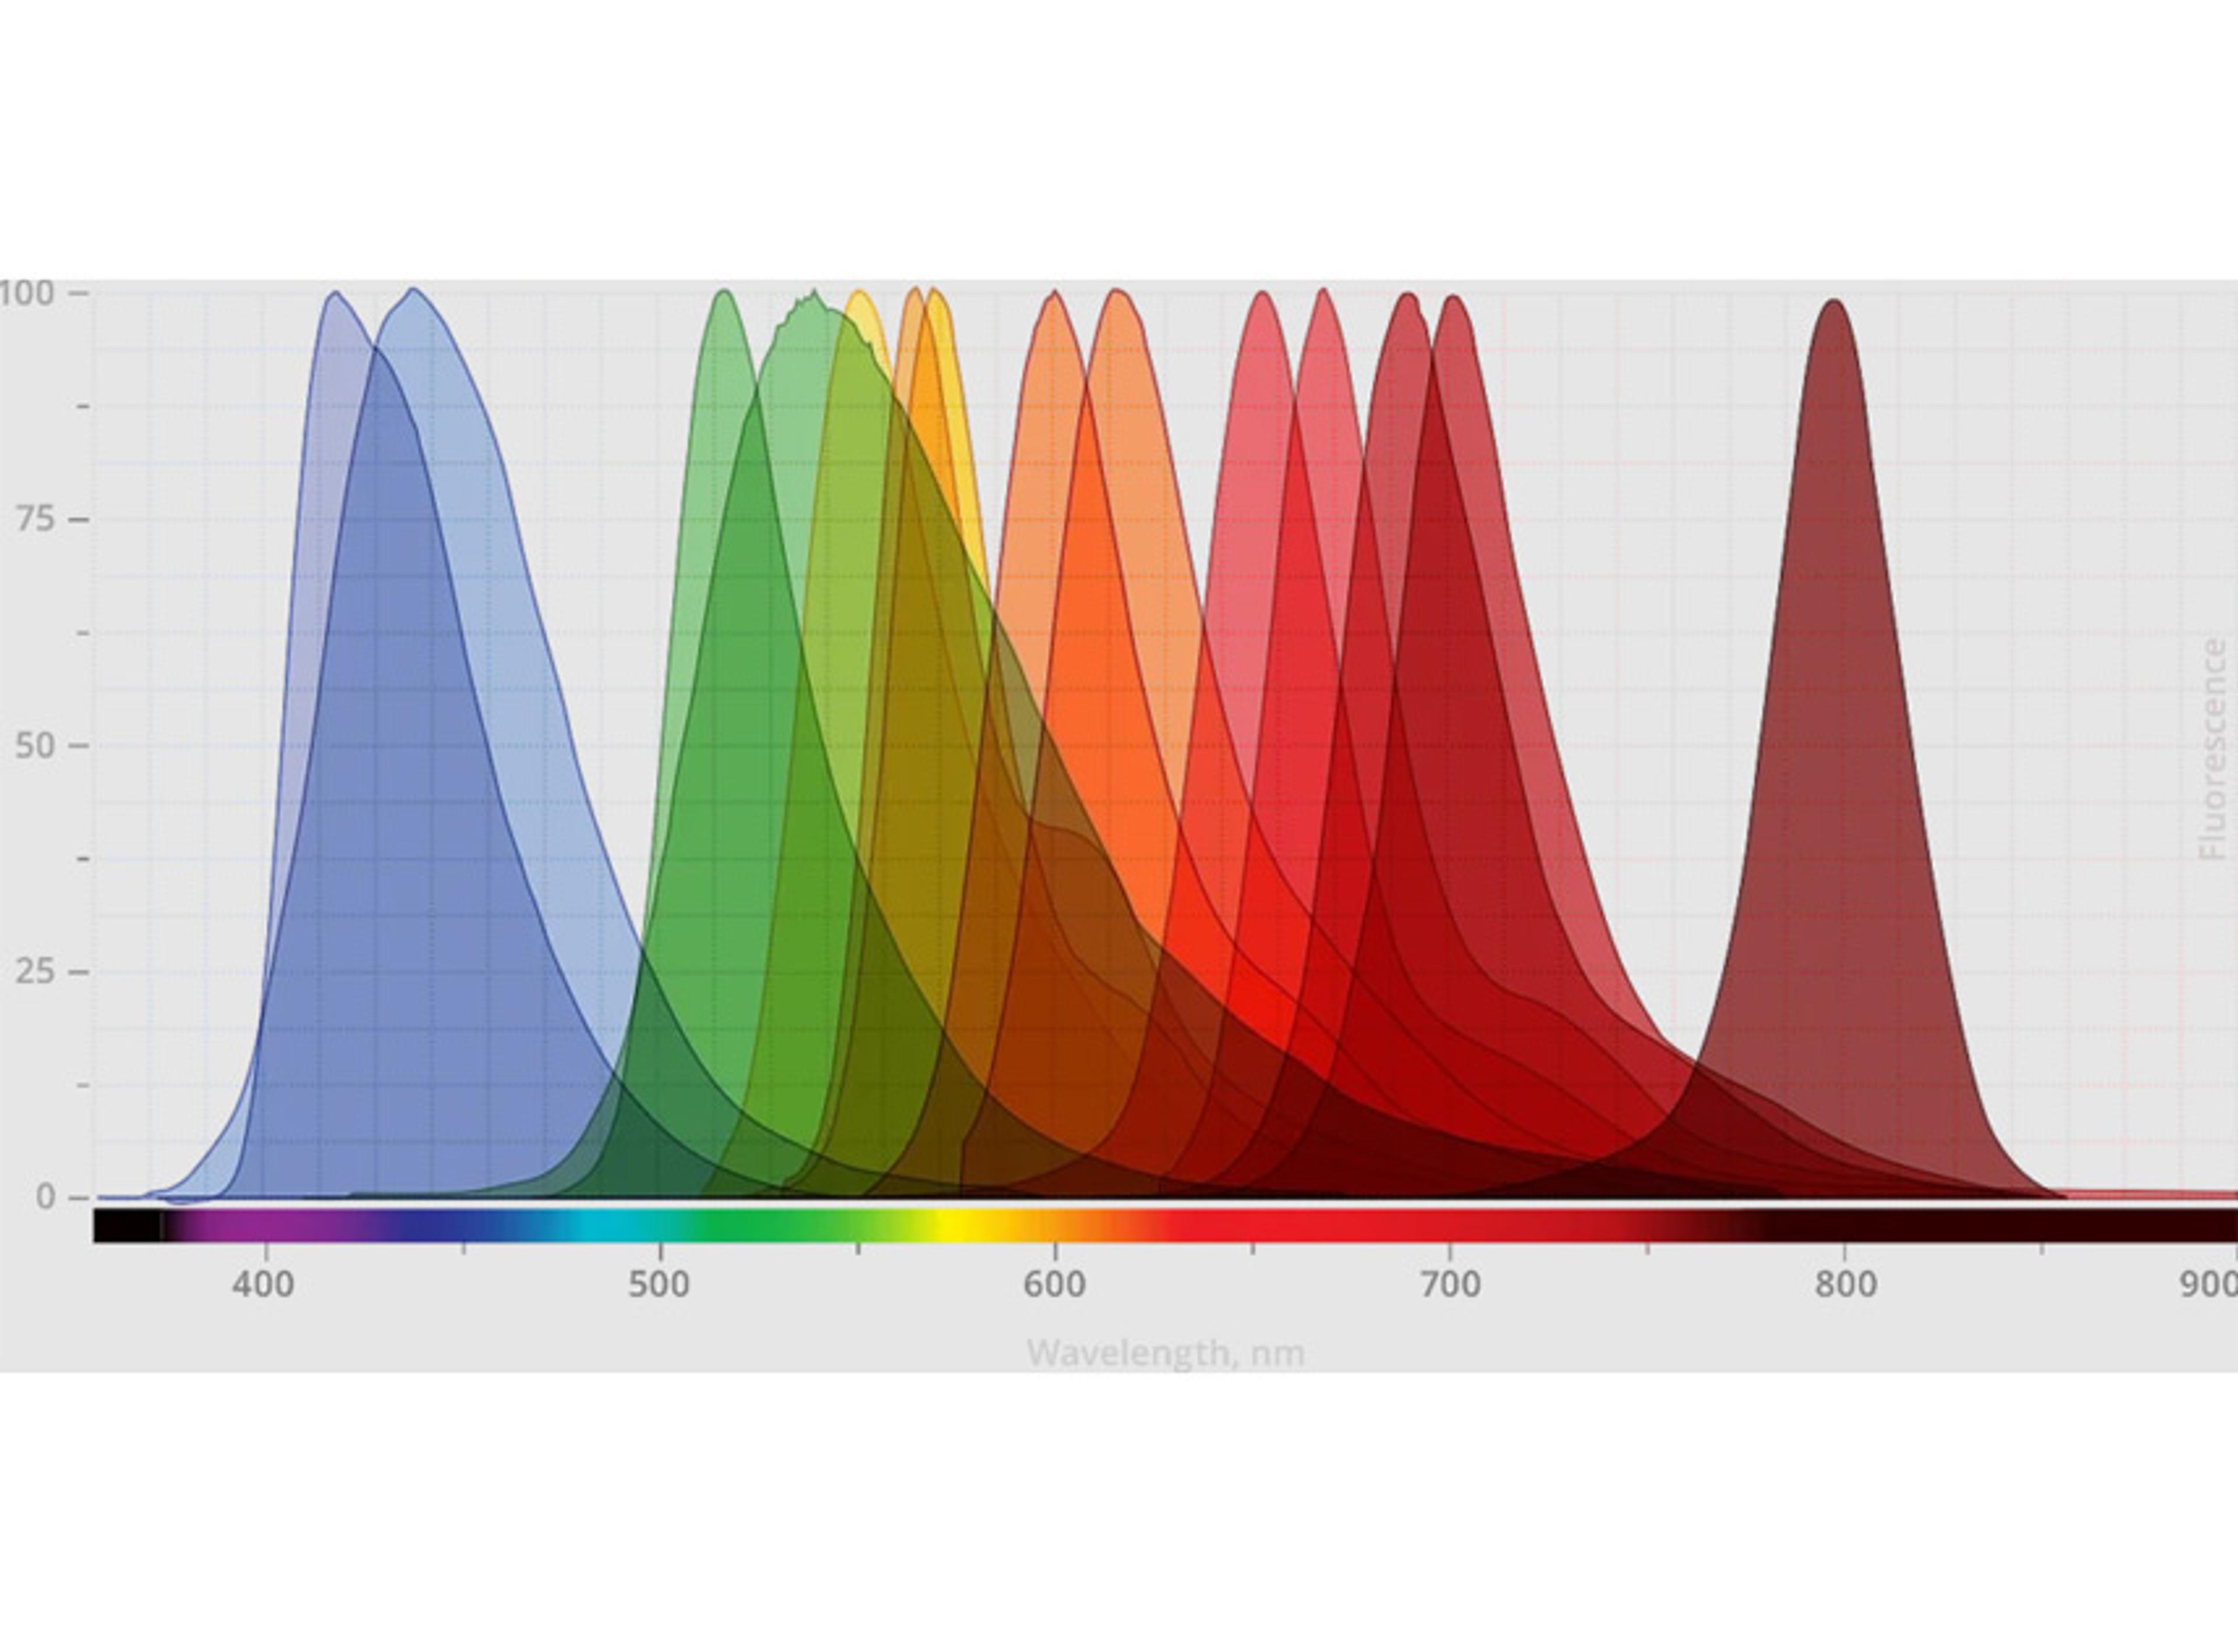

HALO AI is a collection of train-by-example classification and segmentation tools underpinned by advanced deep learning neural network algorithms. HALO AI classifiers can be trained to quantify tissue classes, to segment tissue classes for analysis with other HALO image analysis modules, to find rare events or cells in tissues, and to categorize cell populations into specific phenotypes.

HALO AI is fully integrated with the intuitive, easy-to-use HALO and HALO Link viewers and employs a simple three-step workflow. After defining what tissue classes or cell phenotypes you would like to segment, you train the neural network by drawing annotations – no computer programming or AI knowledge required. Trained classifiers can be applied to segment tissue and cells on any whole slide image or region of interest.

EXCEPTIONAL CELL CLASSIFICATION

Segment nuclei with the new Segmentation classifier. Utilize HALO AI’s pretrained networks for H&E, single IHC, or DAPI stained images for an out of the box solution. Or train your own nuclei segmentation network for a specific application (unique tissue or advanced staining protocols). Once nuclei are segmented, take it a step further using the Nuclei Phenotyper classifier to automatically assign cells into user defined phenotypes with a few quick training examples.